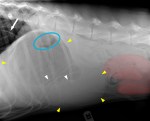

GDV classique